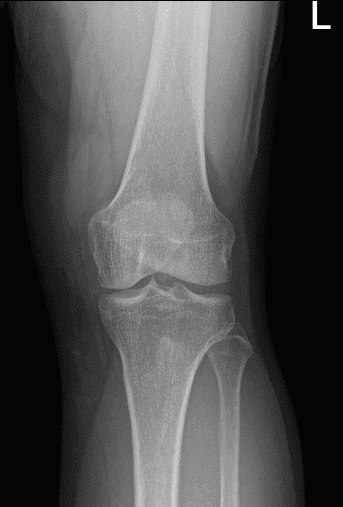

He presented his X-ray and discussed the results. There are no degenerative changes found. However, fracture of enthesophyte arising from the proximal patellar tendon.